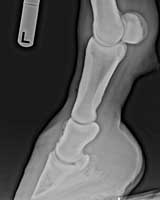

Colleen Cornett and EasyAn update on my horse Easy. GOOD NEWS... I just started him on my last refill bag and I am sure I will not need any more Ringbone Formula. He has not limped for at least 7 weeks now on maintenance dosage of 4 scoops a day. We have been riding him barefoot again for at least 2 months and have tested him out in the hills nearby. (His limping first showed up whenever he was going down a hill.) His ringbone was confirmed by x-rays by our local Vet. It has now been a little over 5 months and I am now tempted to take him back for some "after" x-rays but would rather spend the money on more of your formulas....